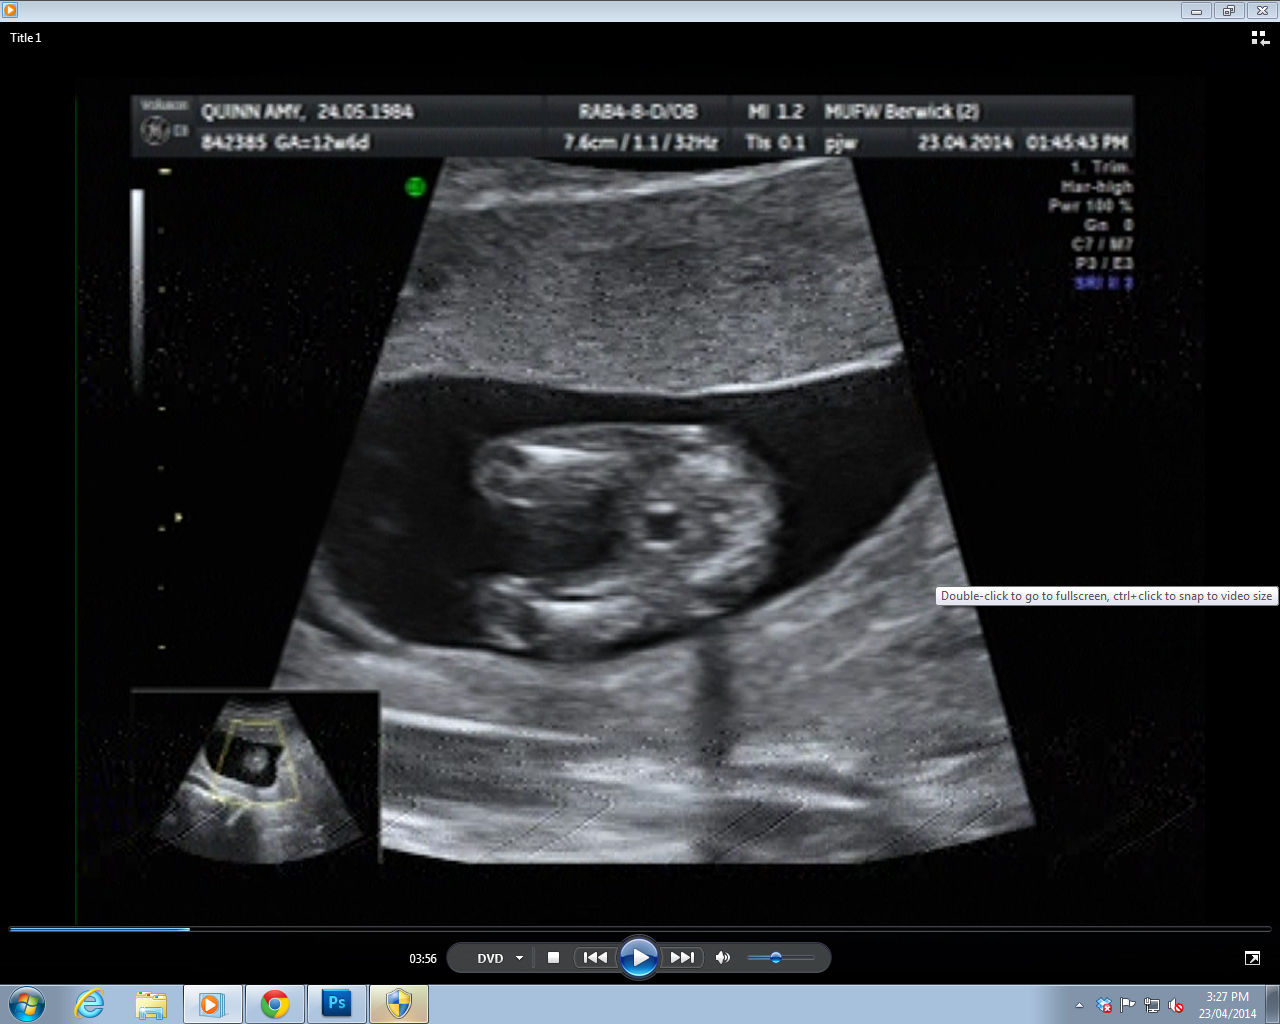

Potty shot 1 - I can just see a protopenis in this one, although it's as blurry as...

Attachment 18366